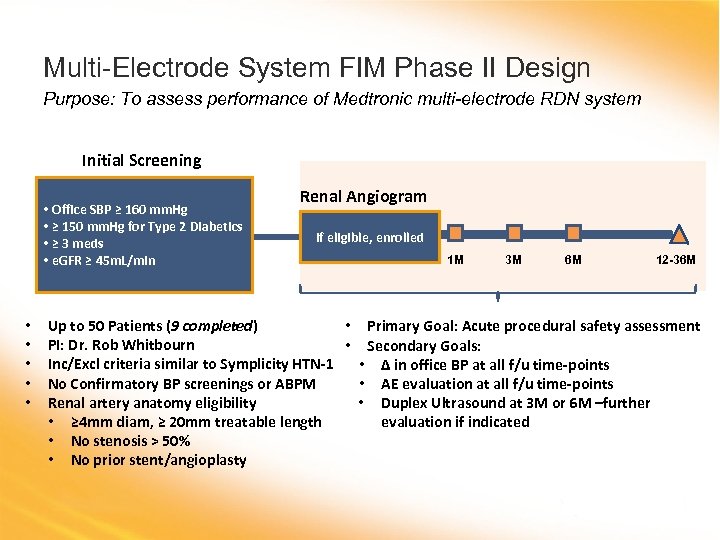

Multi-Electrode System FIM Phase II Design Purpose: To assess performance of Medtronic multi-electrode RDN system Initial Screening • Office SBP ≥ 160 mm. Hg • ≥ 150 mm. Hg for Type 2 Diabetics • ≥ 3 meds • e. GFR ≥ 45 m. L/min • • • Renal Angiogram If eligible, enrolled 1 M 3 M 6 M 12 -36 M Up to 50 Patients (9 completed) • Primary Goal: Acute procedural safety assessment PI: Dr. Rob Whitbourn • Secondary Goals: Inc/Excl criteria similar to Symplicity HTN-1 • Δ in office BP at all f/u time-points No Confirmatory BP screenings or ABPM • AE evaluation at all f/u time-points Renal artery anatomy eligibility • Duplex Ultrasound at 3 M or 6 M –further • ≥ 4 mm diam, ≥ 20 mm treatable length evaluation if indicated • No stenosis > 50% • No prior stent/angioplasty

Multi-Electrode System FIM Phase II Design Purpose: To assess performance of Medtronic multi-electrode RDN system Initial Screening • Office SBP ≥ 160 mm. Hg • ≥ 150 mm. Hg for Type 2 Diabetics • ≥ 3 meds • e. GFR ≥ 45 m. L/min • • • Renal Angiogram If eligible, enrolled 1 M 3 M 6 M 12 -36 M Up to 50 Patients (9 completed) • Primary Goal: Acute procedural safety assessment PI: Dr. Rob Whitbourn • Secondary Goals: Inc/Excl criteria similar to Symplicity HTN-1 • Δ in office BP at all f/u time-points No Confirmatory BP screenings or ABPM • AE evaluation at all f/u time-points Renal artery anatomy eligibility • Duplex Ultrasound at 3 M or 6 M –further • ≥ 4 mm diam, ≥ 20 mm treatable length evaluation if indicated • No stenosis > 50% • No prior stent/angioplasty